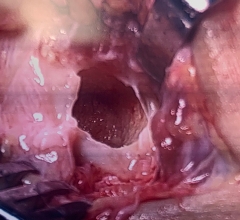

Cored recipient site of talus

In an OATS and cartilage and bone plug is taken from another part of the knee or from a cadaver and it is transplanted to a focal area that lacks cartilage. In order to prepare the cartilage defect for implantation of the OATS, an instrument is used to core out a recipient site for the implantation.